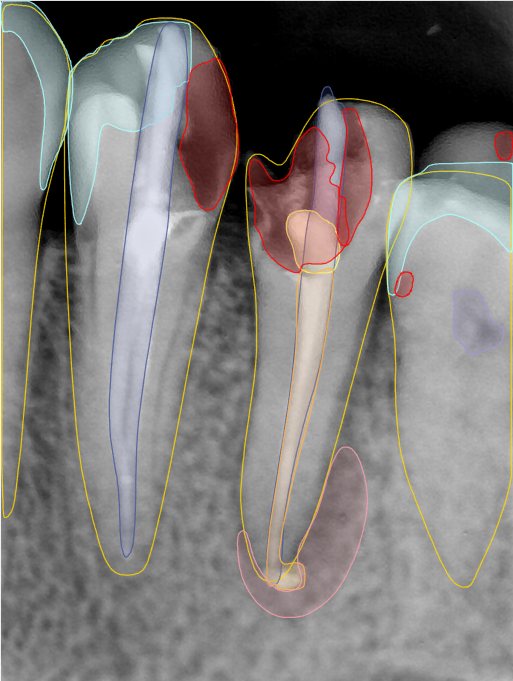

CR/DR 牙齿分割阶段记录

当前进展

- 完成了 CR/DR 牙齿相关分割训练

- 当前结果已经达到阶段预期,但仍有细节问题需要继续处理

相关测试

遇到的问题

- 训练过程中出现过 mask 下移问题

- 部分结果会出现 box 填充异常

- mask 边缘仍然有比较明显的锯齿感

参考

第二版算法问题测试